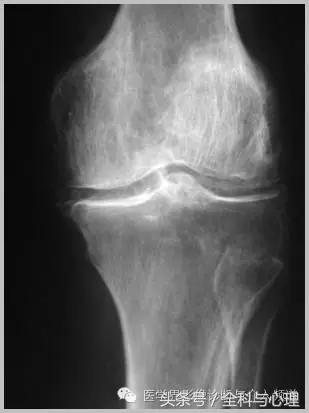

四、软骨来源的钙化:

常见于膝盖、耻骨联合、臀部、尺骨三角纤维软骨复合体、肩关节。

软组织钙化与骨化,软组织钙化和骨质增生 半月板钙化